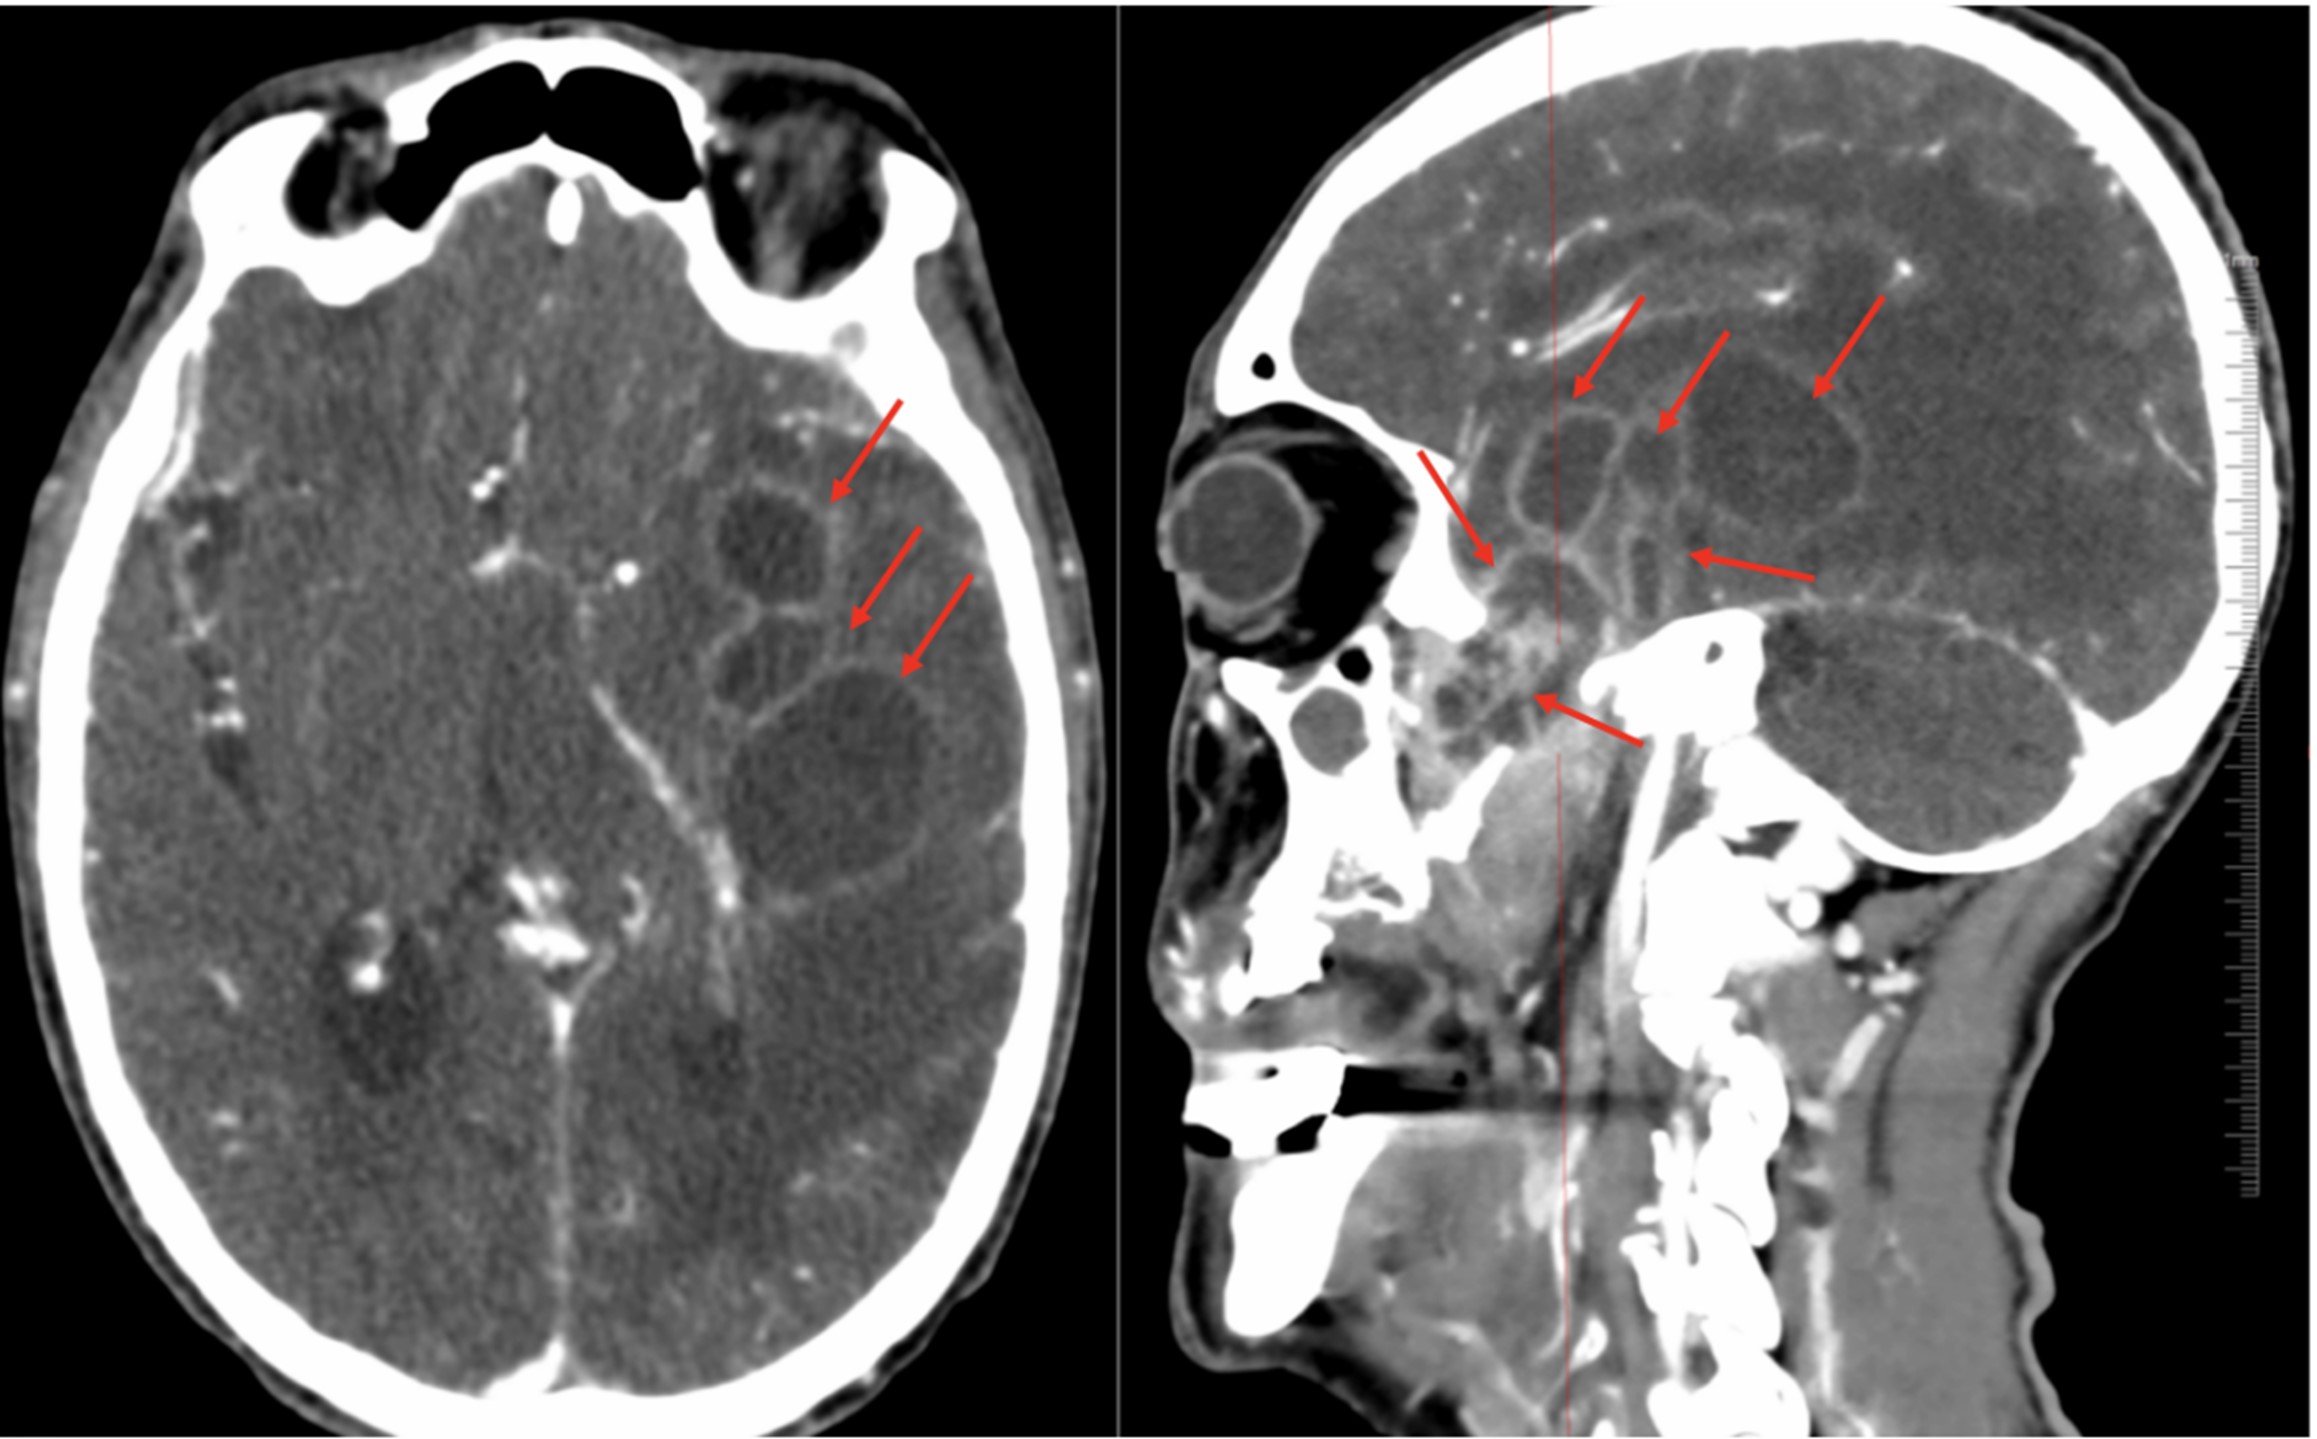

A 76-year-old man developed left temporoparietal pain with intermittent fever in January 2025. One month later, his condition worsened, with fever up to 39 °C, slowed responsiveness, disorganized speech, drowsiness, and poor cooperation on examination. He had a history of colorectal cancer surgery in 2006 with good recovery and no chemotherapy or targeted therapy. Laboratory tests performed upon admission showed elevated white blood cell count (WBC, 12.18 × 109/L), neutrophil (NEU%, 85%), high-sensitivity C-reactive protein (hsCRP, 38.71 mg/L), procalcitonin (PCT, 0.107 μg/L), and interleukin-6 (IL-6, 80.36 ng/L), along with reduced lymphocyte percentage (LYM%, 8.9%) and hemoglobin (Hgb, 87 g/L). Cranial CT revealed abscesses in the left frontal, temporal, and parietal lobes and the lateral ventricles, with right-sided hydrocephalus; chronic inflammation was present in the bilateral maxillary sinuses, left ethmoid sinus, and sphenoid sinus (Figure 1). Based on the laboratory results (i.e., elevated levels of inflammatory markers) and the imaging findings (i.e., cerebral abscesses), empirical antibacterial therapy and dehydration for intracranial pressure reduction were initiated. On day 4 of admission, endoscopic surgery was performed to remove lesions in the left sphenoid sinus–pterygopalatine fossa–middle cranial base. A direct smear of sphenoid tissue revealed septate hyphae with 45° branching (Figure 2). The presence of A. fumigatus was confirmed via culture and VITEK MS identification (Figure 3AC). Cerebral Aspergillus abscess was thus considered, and voriconazole was initiated at a loading dose of 300 mg administered intravenously every 12 h, followed by a maintenance dose of 200 mg administered intravenously every 12 h. On day 7, repeat surgery was performed to reduce multiple intracranial abscesses via external ventricular drainage. Smear and culture of temporal lobe abscess samples showed that A. fumigatus was present. Histopathological analysis of sphenoid sinus and temporal lobe abscess samples showed brain tissue necrosis with extensive acute and chronic inflammatory cell infiltration and granuloma formation, as well as fungal clusters (Figure 4). Periodic acid–Schiff (PAS) stain and Grocott's methenamine silver (GMS) staining returned positive results. After treatment, the patient's mental status, headaches, and fever improved, and his muscle strength and tone in all four limbs were normal. On day 15, the laboratory test results showed a marked reduction in inflammatory markers. However, the patient was lost to follow-up after discharge (on day 25).

Figure 1

Figure 1. Cranial CT images showing cerebral abscesses in the left fronto-temporo-parietal lobe and lateral ventricle, hydrocephalus in the right hemisphere (red arrows), and chronic inflammation of the bilateral maxillary sinuses, left ethmoid sinus, and sphenoid sinus. CT, computerized tomography.